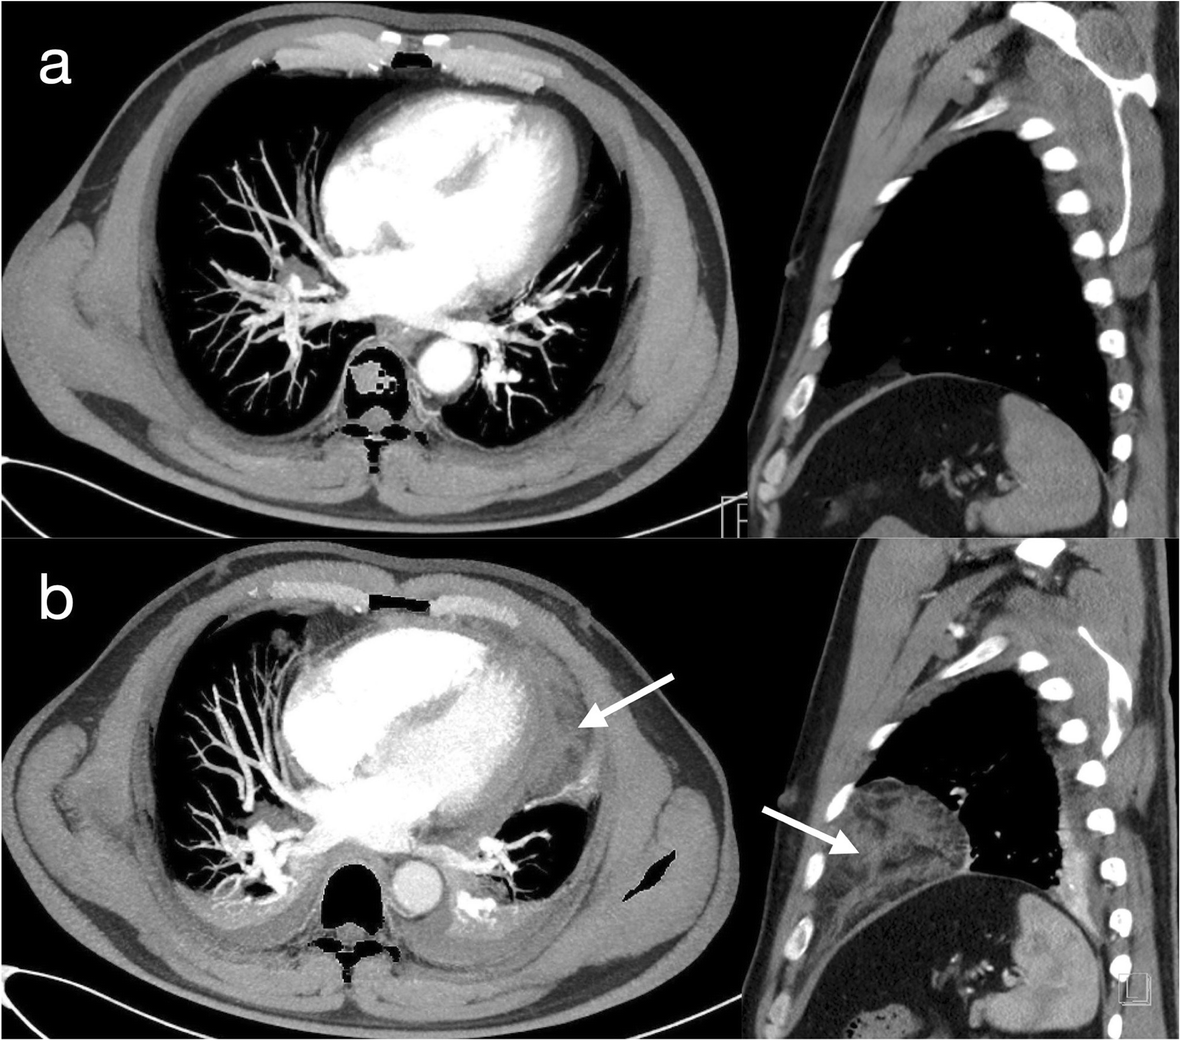

Fig. 2

From: Mediastinal effusion due to pericardiocentesis with cardiac tamponade: a case report

Computed tomography pulmonary angiography

No mediastinal effusion occurred before the pericardiocentesis (Panel a). The white arrow shows the mediastinal effusion after the pericardiocentesis (Panel b)